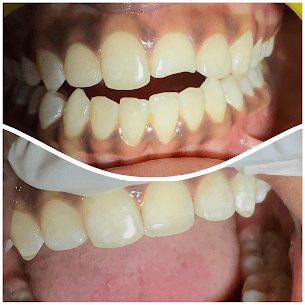

- TREATMENTS:

Quick Composite Solution

- INFO:

30-minute painless composite treatment for midline space closure